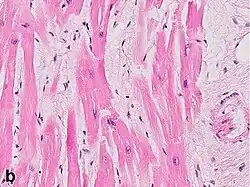

Under the microscope, myocardial infarction presents as a circumscribed area of ischemic, coagulative necrosis (cell death). On gross examination, the infarct is not identifiable within the first 12 hours.[22]

Although earlier changes can be discerned using electron microscopy, one of the earliest changes under a normal microscope are so-called wavy fibers.[23] Subsequently, the myocyte cytoplasm becomes more eosinophilic (pink) and the cells lose their transversal striations, with typical changes and eventually loss of the cell nucleus.[24] The interstitium at the margin of the infarcted area is initially infiltrated with neutrophils, then with lymphocytes and macrophages, who phagocytose ("eat") the myocyte debris. The necrotic area is surrounded and progressively invaded by granulation tissue, which will replace the infarct with a fibrous (collagenous) scar (which are typical steps in wound healing). The interstitial space (the space between cells outside of blood vessels) may be infiltrated with red blood cells.[22]

These features can be recognized in cases where the perfusion was not restored; reperfused infarcts can have other hallmarks, such as contraction band necrosis.[25]

These tables gives an overview of the histopathology seen in myocardial infarction by time after obstruction.

| Myocardial histologic parameters (HE staining)[26] | Earliest manifestation[26] | Full development[26] | Decrease/disappearance[26] | Image |

| Stretched/wavy fibres | 1–2 h |

| Coagulative necrosis: cytoplasmic hypereosinophilia | 1–3 h | 1–3 days; cytoplasmic hypereosinophilia and loss of striations | > 3 days: disintegration |